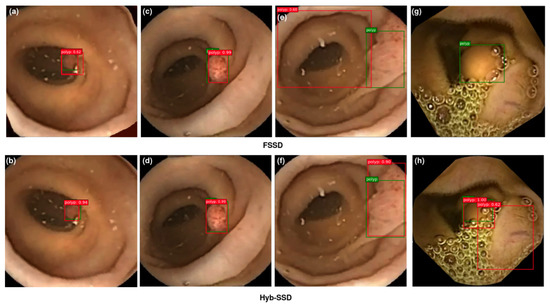

4.4.3. Visualization of Detection Results